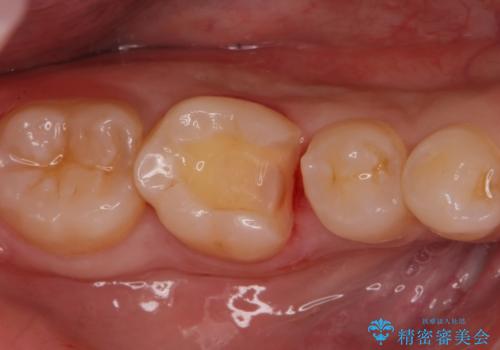

- 銀歯を無くしたいとの事で来院。

メタルを除去し、拡大鏡下で虫歯がない事を確認しe-maxインレーで治療を行いました。